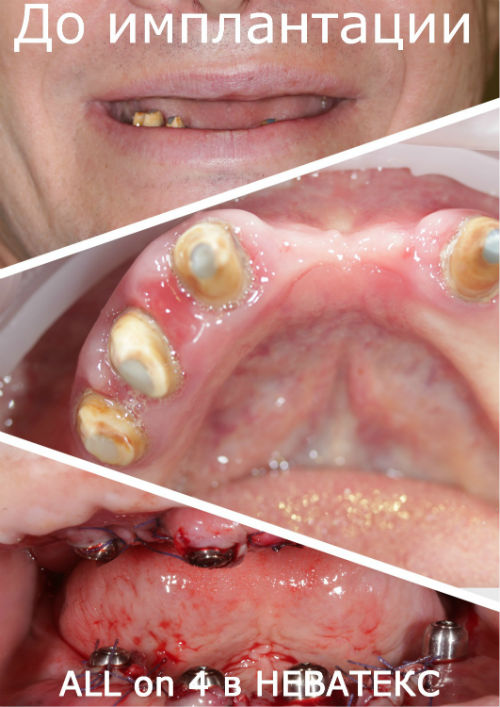

All-on-4 в клинике НЕВАТЕКС.МОСКВА

Зубы за один день фото до и после

Работа сделана в 2012 году

Имплантация: фото ДО и ПОСЛЕ

![]() |

Эти красивые зубы по протоколу ALL ON 4 установлены на 5 й день после операции и включены в стоимость